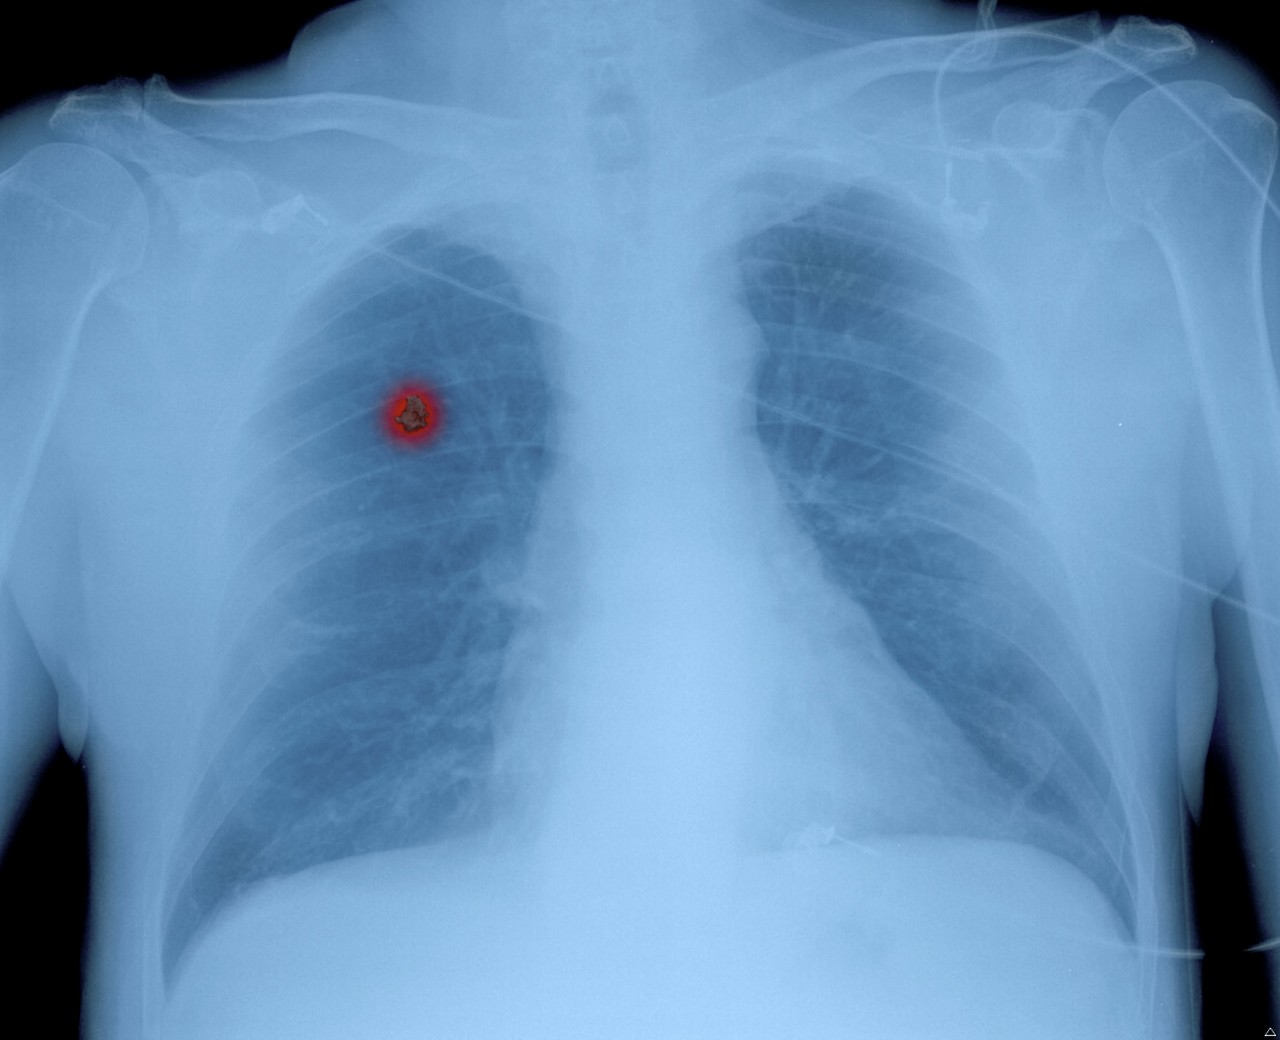

Un "nodule pulmonaire" découvert lors d'un examen physique peut-il réellement se transformer en cancer du poumon ?